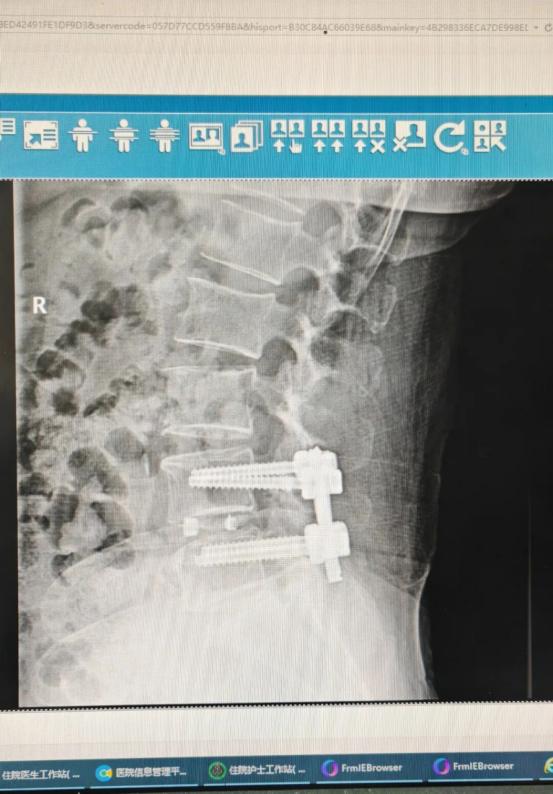

术后复查X线:融合器位置良好,滑脱完全纠正